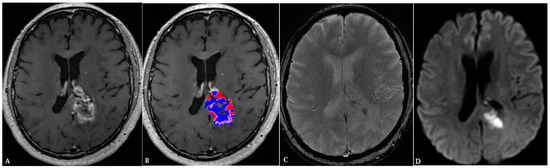

- Lohmann, P.; Kocher, M.; Ceccon, G.; Bauer, E.K.; Stoffels, G.; Viswanathan, S.; Ruge, M.I.; Neumaier, B.; Shah, N.J.; Fink, G.R.; et al. Combined FET PET/MRI radiomics differentiates radiation injury from recurrent brain metastasis. NeuroImage Clin. 2018, 20, 537–542. [Google Scholar] [CrossRef] [PubMed]

- Müller, M.; Winz, O.; Gutsche, R.; Leijenaar, R.T.H.; Kocher, M.; Lerche, C.; Filss, C.P.; Stoffels, G.; Steidl, E.; Hattingen, E.; et al. Static FET PET radiomics for the differentiation of treatment-related changes from glioma progression. J. Neuro-Oncol. 2022, 159, 519–529. [Google Scholar] [CrossRef] [PubMed]